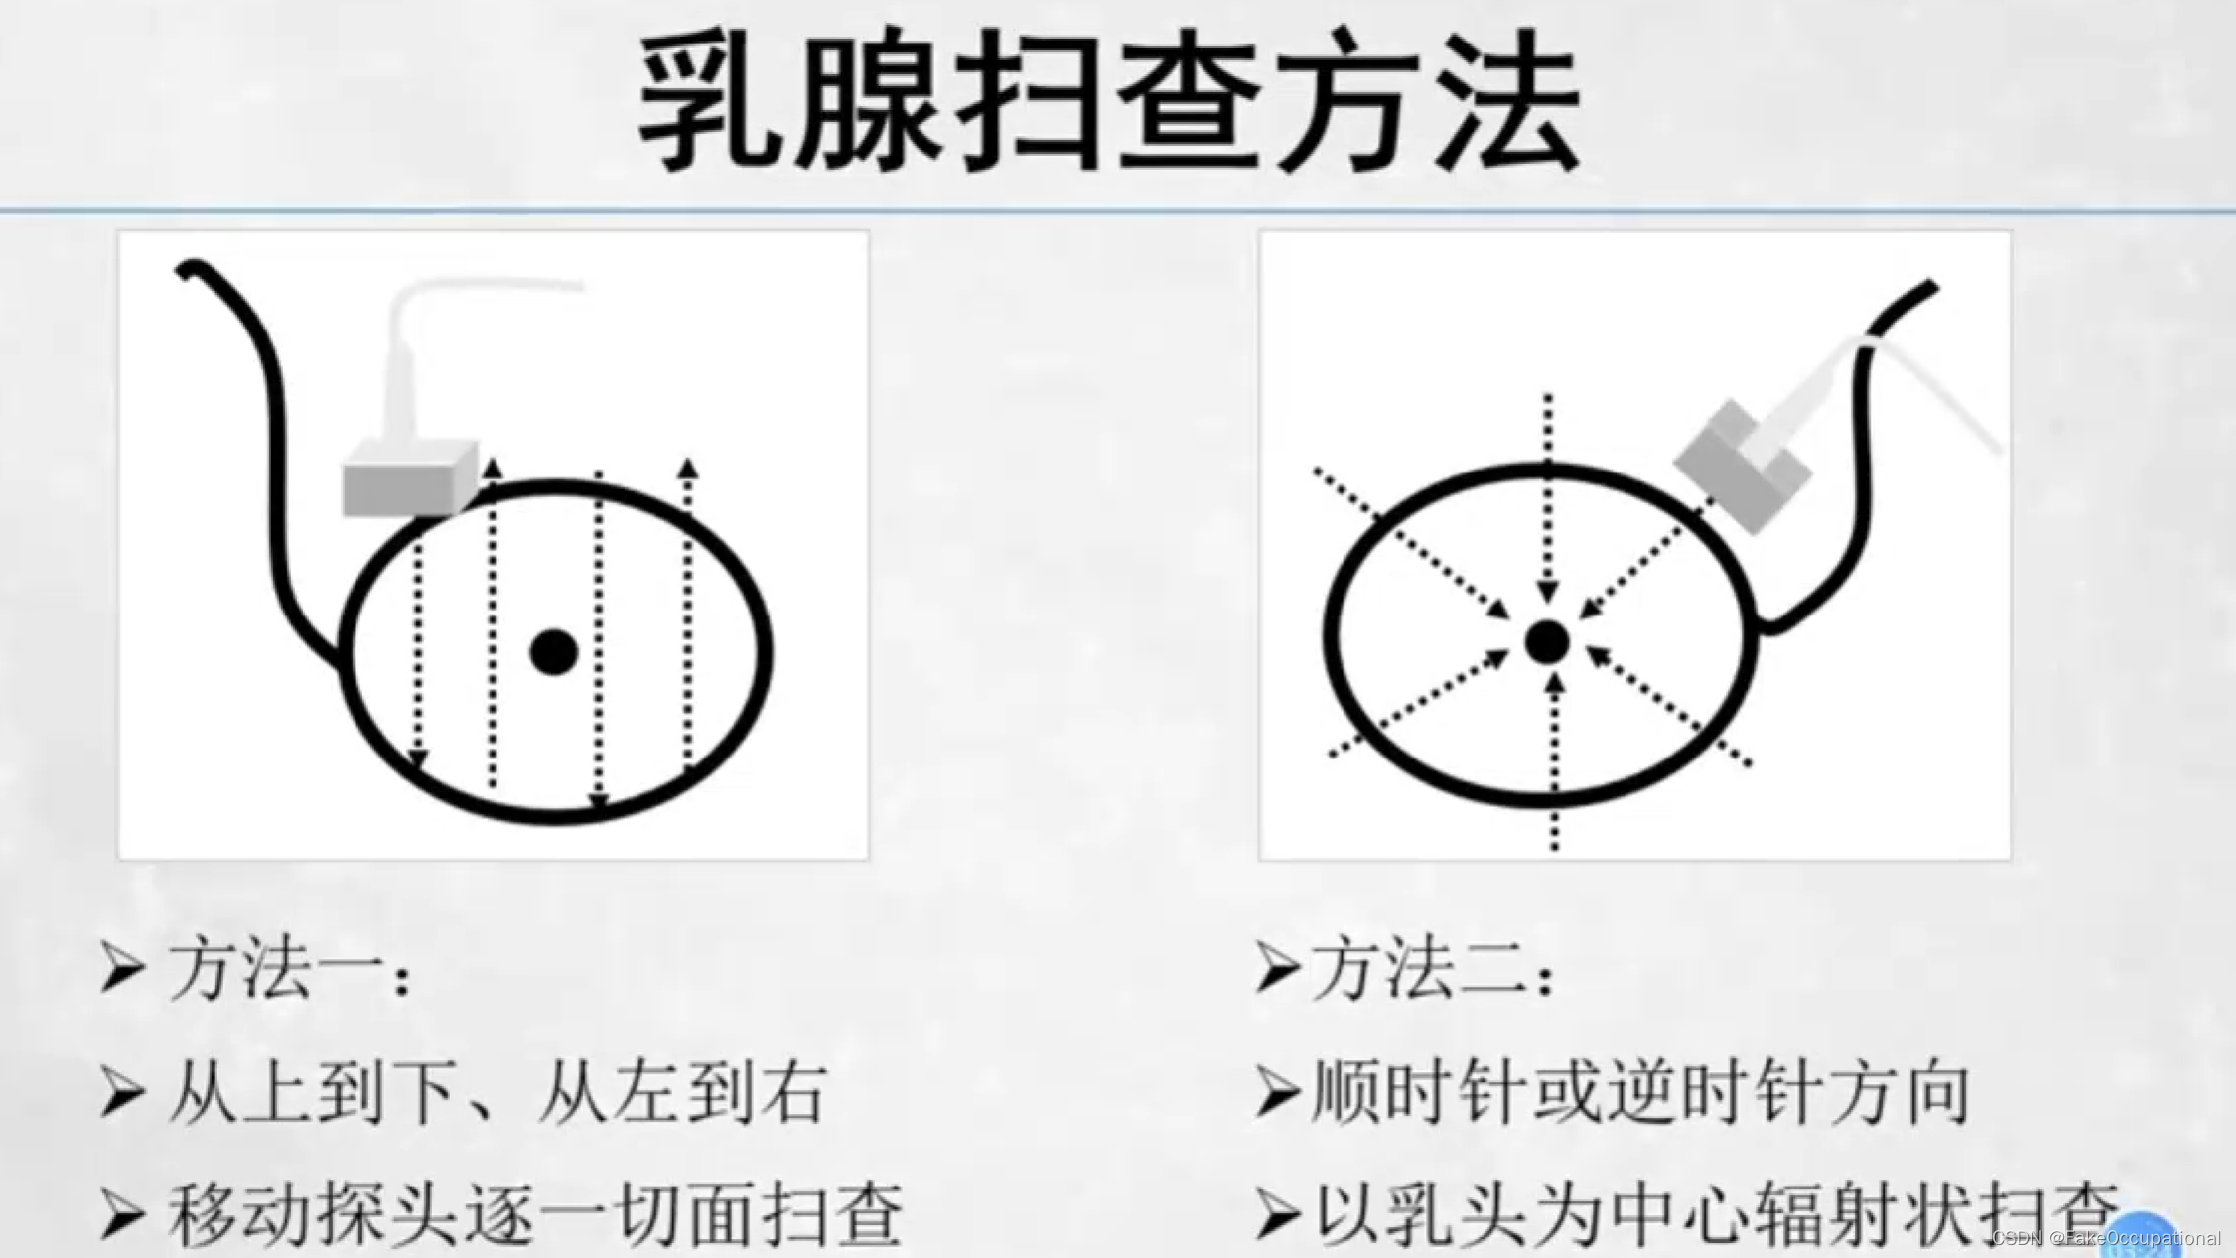

乳腺超声检查技术

- 检查前患者无特殊准备,对月经周期并无太大要求

乳腺检查注意事项

- 双侧对比:检查时先健侧、后患侧

- 避免加压: 探头轻放,以免改变肿块形态、位置或影响肿块内血流显示,必要时加压

- 全面扫查: 乳头后区域适当斜切,必要时可增加耦合剂